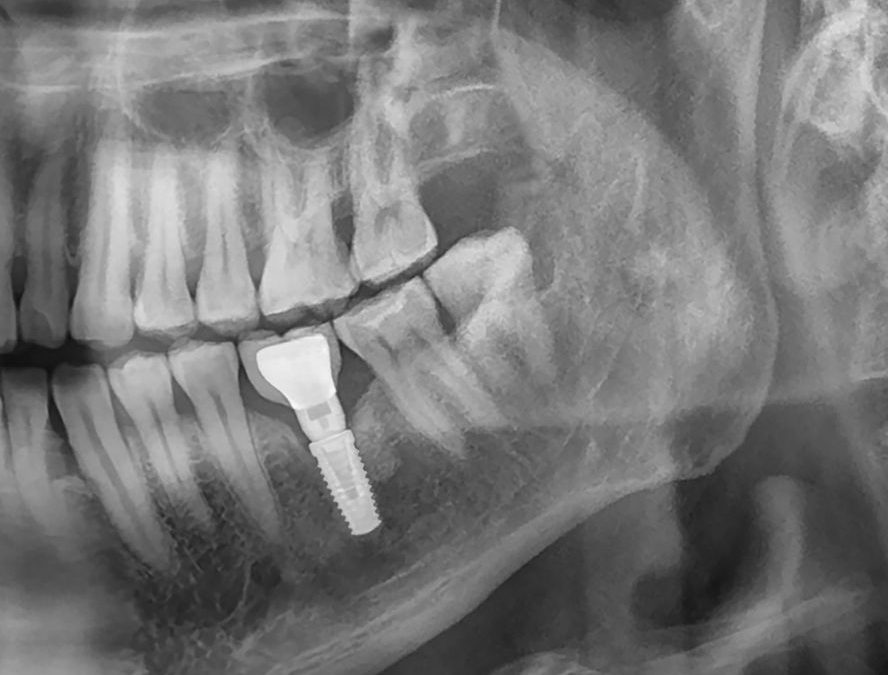

Avant de procéder à l’implantation dentaire, il est essentiel de réaliser un bilan complet de votre santé osseuse. Cela inclut généralement des examens

radiographiques détaillés, comme la radiographie panoramique, pour évaluer la densité et la qualité de l’os.

Lors de cette évaluation, votre dentiste pourra déterminer si vous êtes un bon candidat pour un implant dentaire ou si des procédures supplémentaires, telles qu’une greffe osseuse, sont nécessaires.